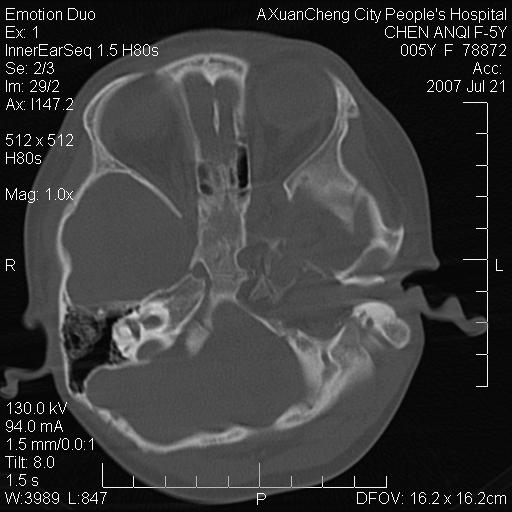

标题: PED0273:5岁,左耳流脓痛疼一周,颅底骨质破坏 [打印本页]

标题: PED0273:5岁,左耳流脓痛疼一周,颅底骨质破坏

患儿5岁,左耳流脓痛疼一周,左外耳道肉芽组织填塞 软组织窗显示病灶内结节状低密度影为气体密度

左侧中耳炎并胆脂瘤,左颞骨岩部骨质破坏并颅内感染积气。

考虑化脓性中耳乳突炎伴胆脂肪瘤形成并左颞叶感染,不除外合并嗜酸性肉芽肿.